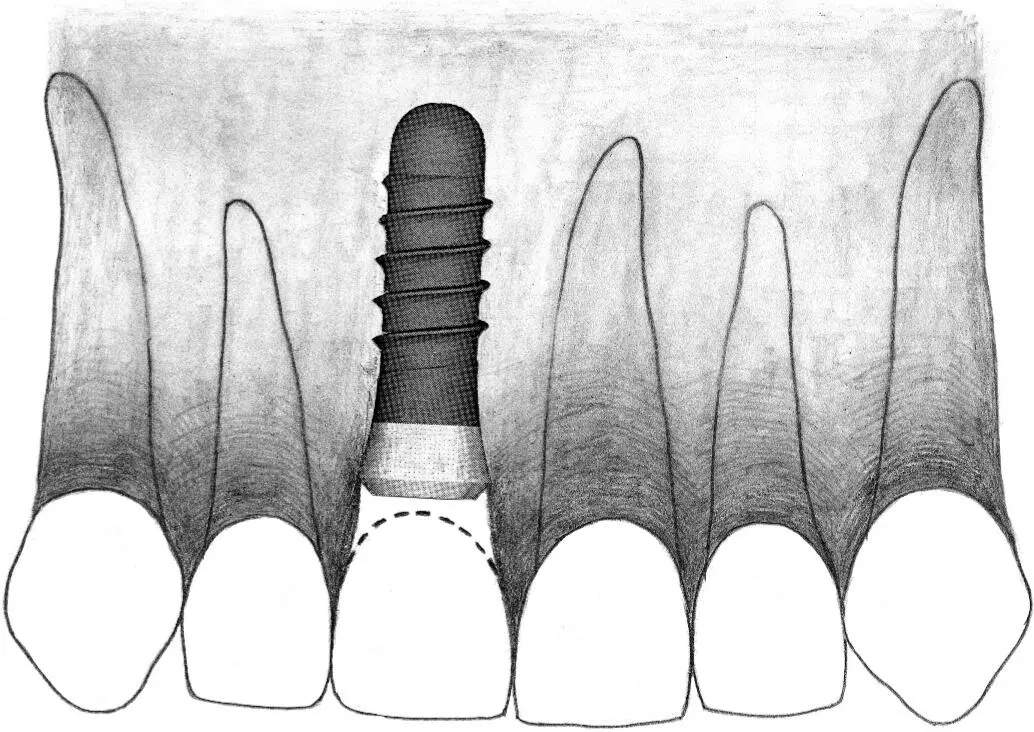

Fig 2-2a In an esthetic restoration involving a single-tooth gap in the anterior region, a standard plus implant is indicated to replace a missing central incisor.

Fig 2-2b A standard plus implant can also be used to replace a maxillary canine in the esthetic zone.